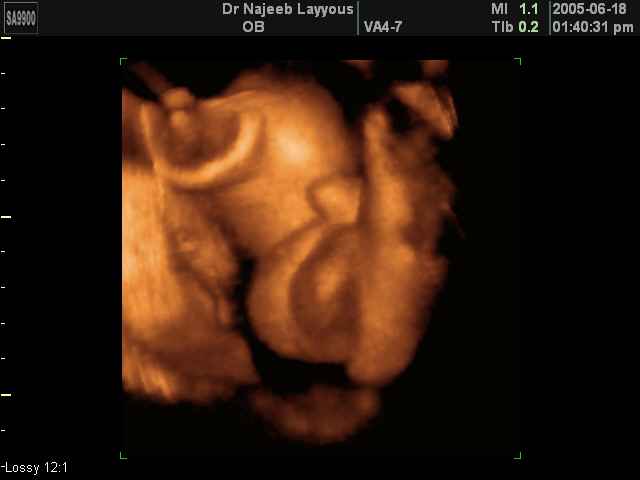

- Fetal Parts Ultrasound Scan Photos